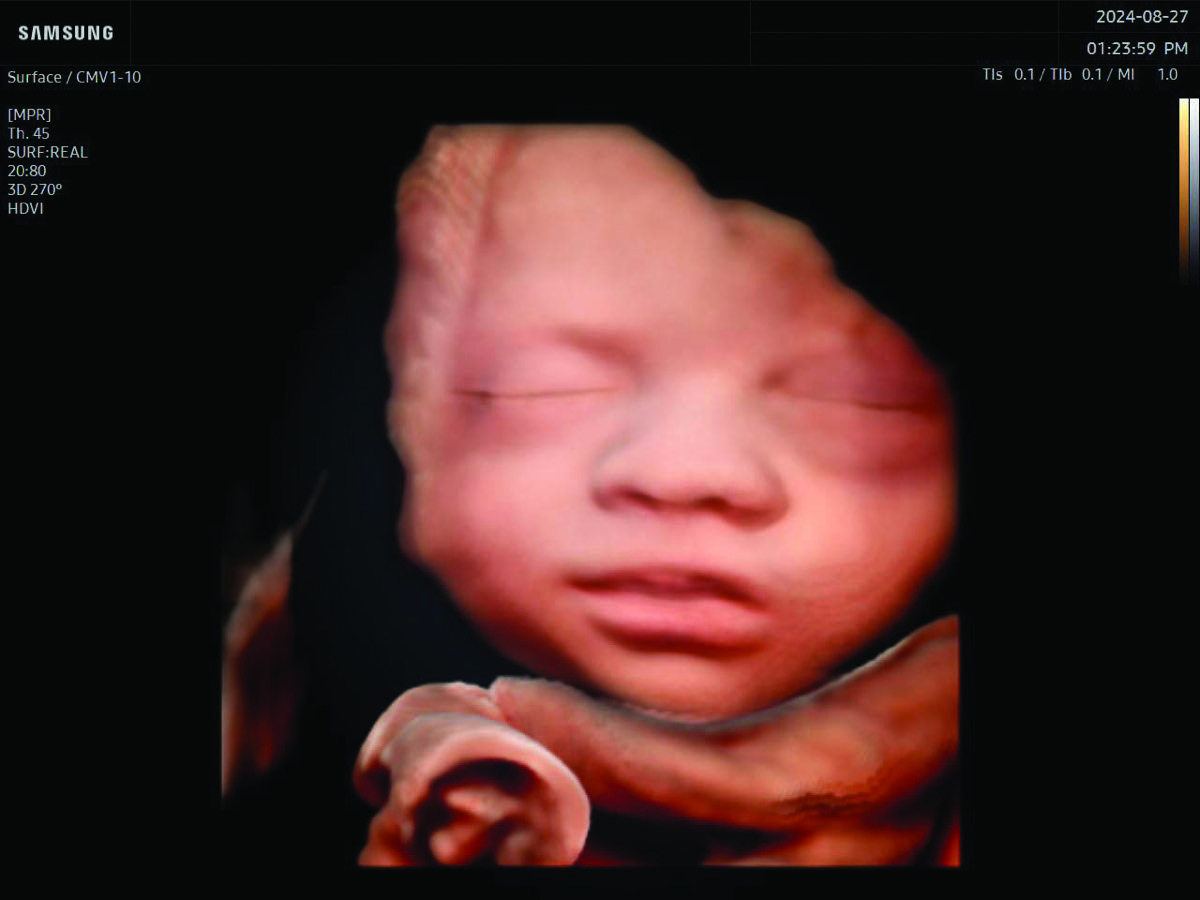

Personalized Care

Comprehensive, advanced and expert MFM care for high-risk pregnancies